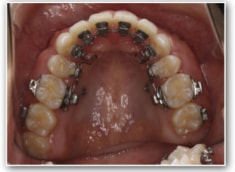

治療法:裏側の矯正(リンガルブラケット:舌側矯正)

治療開始1年後